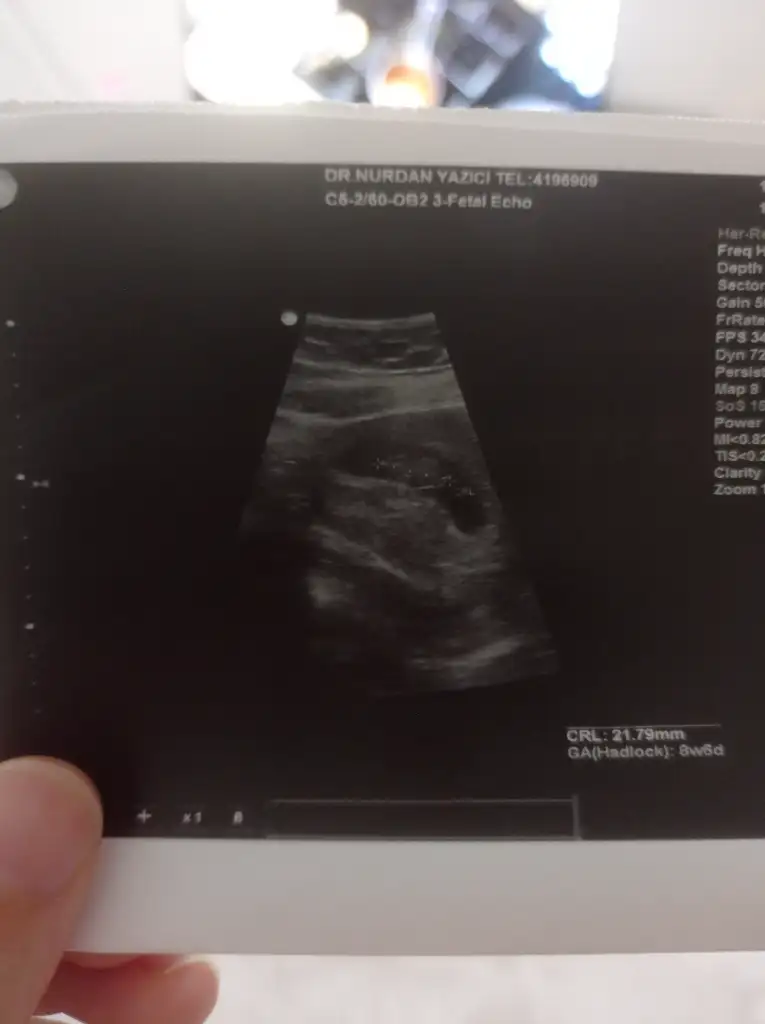

Tatlı kuşum hiç üzülme bu farklılıklar çok normal inan, herkeste olan bi farklılık daha çok minik dediği gibi kesende gayet iyi bence :) maşallah, sen sadece kan pıhlaşması için mi kan verdin yoksa kromozom içinde verdin miKızlar ben de bugün Dr a gittim 4+6 benim hesabıma gore fakat Dr +6 si yok tam 4 hafta görünüyor dedi 6 mm dedi çok küçük daha dedi. Biraz gerdi beni bu durum1 hafta sonra gel dedi..

Kuzu az bulmamıştır sat ile aynı gitmiyor demiştir Buda çok normal bi durum zaten gayette normal merak etme sen, her zaman tam destek ne zaman istersenÇok teşekkür ederim destegin içinSadece pıhtılaşma icin aldı canım başka şey istemedi sanırım çünkü tek tüp kan verdim. Ben de baktım burda herkes chatgbt sormuş ben de indirdim sordum normal dedi 6mm ama Dr niye az buldu kafamda deli sorular

Senin kese maşallah büyükmüş benim 8mm çıktı ama kalp atışını duydum bilmiyorum korkuyorumMerhaba ben geçen hafta kese görmeye gittim 11mm ve 5 haftalık dedi doktorum. İlerleyen günlerde yerleşme kanaman olabilir korkma dedi. Bende şaşırdım geç değil mi diye geçirdim içimden. Belki seninde öyle bir durum vardır yani hemen olumsuz düşünme sonuçta pembe akıntın olmuş